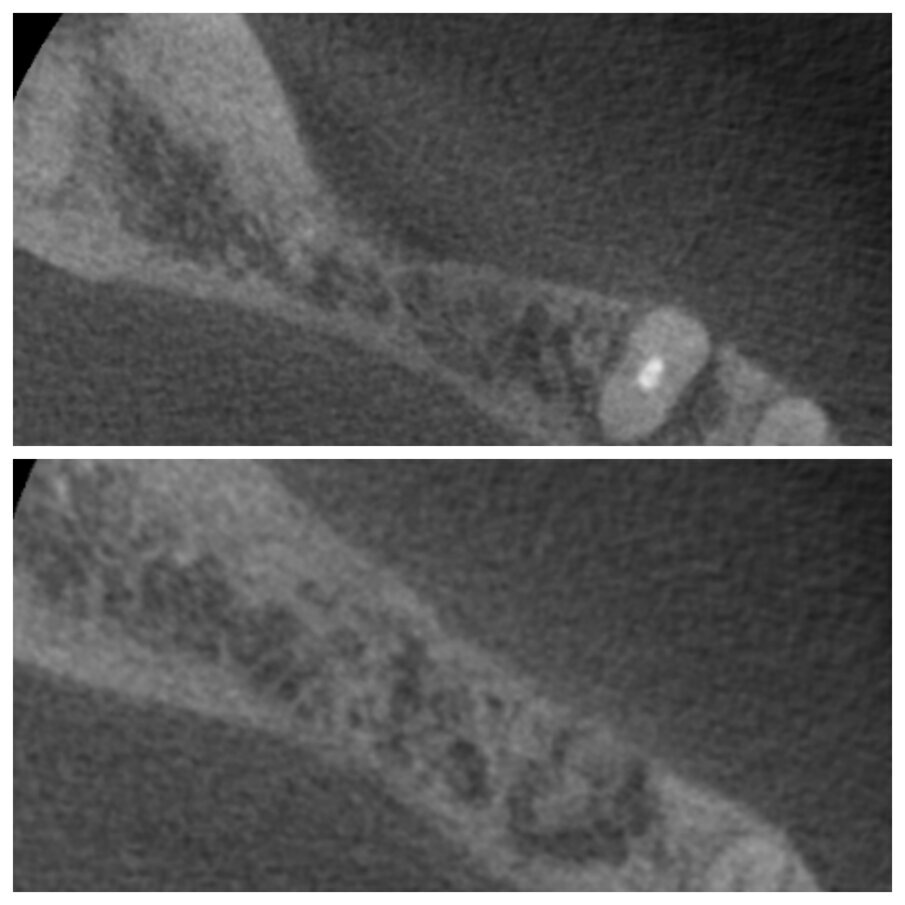

Fig. 3a_Tecnica S.A.T. applicata in zona 44-45-46.

Fig. 3d_Qualità del tessuto neoformato e posizionamento implantare.

Tutti gli interventi eseguiti con questa tecnica, nove in tutto, hanno portato alla risoluzione del deficit orizzontale presente al momento dell’estrazione, e hanno permesso in tutte le zone trattate un buon inserimento implantare senza la necessità di ulteriori tecniche di GBR (Figg. 1d, 3a, 3d, 6b). Gli interventi sono stati eseguiti sia in mandibola che nel mascellare superiore, trattando edentulie singole e multiple. Non eseguendo lembi di scarico e scollando il meno possibile, i pazienti nei giorni successivi non presentano particolare gonfiore; anche il dolore è molto limitato e gestibile con poche dosi di antidolorifico per via orale, oltre la terapia antibiotica con Amoxicillina 875 mg. e Acido Clavulanico 125 mg. ogni 12 ore per sei giorni. Il primo caso risale al gennaio 2011 ed abbiamo quindi un controllo a più di 4 anni dal posizionamento implantare (Fig. 7). La stabilità dei tessuti duri e molli è risultata buona, non avendo perso alcun impianto e soprattutto non avendo casi di perimucosite-perimplantite.

La tecnica semplificata di apposizione del biomateriale (S.A.T.) permette di ripristinare il deficit orizzontale presente a fianco di un dente da estrarre nel modo meno invasivo possibile, facendosi guidare nell’innesto dall’anatomia del sito da ricostruire (Fig. 3c). A distanza di sei mesi i tessuti cheratinizzati sono sempre presenti in ottima quantità (Figg. 1b, 2b, 3b) ed il biomateriale è sempre apparso ben integrato con l’osso nativo sottostante anche senza bisogno di forare la corticale, in questo sicuramente l’alveolo zeppato garantisce un input osteoinduttivo. La stabilità dell’innesto è garantita dalla mancanza di scarichi mesiali o distali, in pratica la busta creata è un sito contenitivo a 4 pareti. Così come risulta fondamentale ricostruire un sito post estrattivo immediato per evitare un collasso dei tessuti duri e molli in senso orizzontale e verticale, è altrettanto importante avere a disposizione una tecnica semplice e poco invasiva per ripristinare contestualmente siti atrofici ereditati da guarigioni precedenti (Figg. 1e, 3e). I risultati avuti finora sono molto buoni e non si sono verificati effetti avversi; ovviamente i numeri dovranno crescere così come i controlli nel tempo (Fig. 6c). Oltre a questo, sarebbe interessante applicare la stessa tecnica di aumento orizzontale dove non vi siano elementi da estrarre ma solo creste guarite con deficit orizzontale, questo amplierebbe considerevolmente le applicazioni di questa tecnica, anche se i risultati mostrati ultimamente dalla tecnica S.M.A.R.T.® incoraggiano nei siti edentuli un approccio laterale.